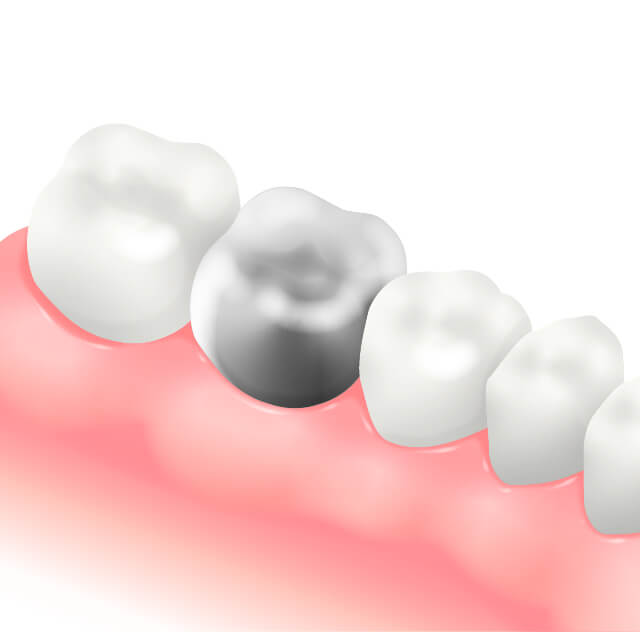

メタルインレー(詰め物)

奥歯の中等度以上のむし歯に対して行う詰め物で、型をとり技工士に作製してもらいはめ込むため治療回数がかかる。

また、金属は年数の経過とともに変形するため隙間ができる可能性が高く、その隙間から細菌が侵入し、むし歯が再発してしまう可能性がある。審美性も優れない。

メタルクラウン(奥歯被せ物)

奥歯に対しての被せ物。メタルインレーでは対応できない大きなむし歯や根管治療終了後のケースに使用される。

金属は年数の経過とともに変形するため隙間ができむし歯が再発してしまう可能性がある。

また、金属なので審美的に優れない。